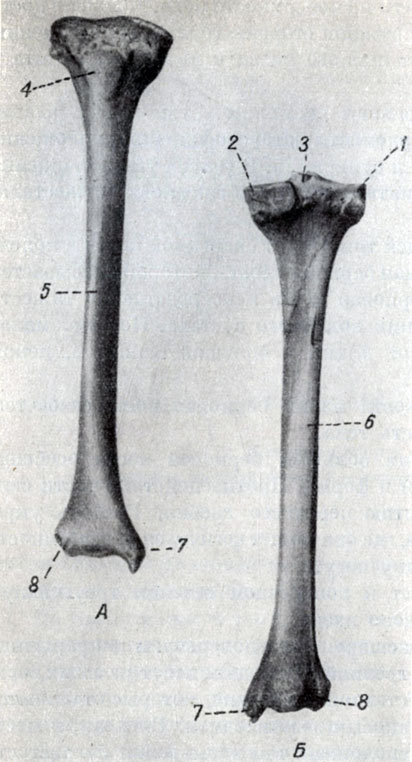

Анатомия фибулы: Подробные фотографии и схемы